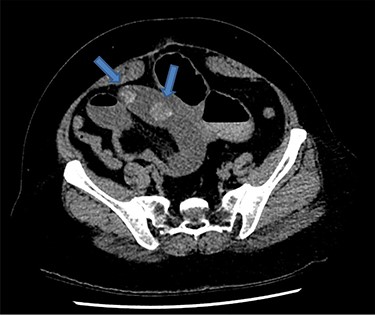

There were associated vomiting and abdominal distension. Her last bowel movement was 12 hours prior to the presentation, and she passed minimal flatus since. She has a background of chronic kidney disease. She was slightly tachycardic in ED. Abdominal examination demonstrated a mildly distended and soft abdomen with left lower quadrant tenderness without peritonism. Blood work showed an acute on chronic renal failure (creatinine 198 μmol/l and estimated glomerular filtration rate 24 ml/min/1.73 m2). Liver function tests were mildly deranged (bilirubin 27 μmol/l, alkaline phosphatase 105 U/l, GGT 85 U/l, alanine aminotransferase 38 U/l, aspartate aminotransferase 37 U/l) and white cell count was slightly elevated (10.7 × 109/l; reference range 3.7–9.5 × 109/l). Computed tomography (CT) scan (Figs 1 and 2) demonstrated multiple loops of moderated dilated small bowel. There were two 25-mm gallstones in a loop of small bowel in the right lower quadrant. The gallbladder is collapsed with intraluminal gas. There was pneumobilia in the biliary tree. The features on CT are in keeping with a gallstone ileus. Initial management included fluid resuscitation, insertion of a nasogastric tube, analgesia and nil by mouth. A Foley catheter was inserted to monitor urine output. A laparotomy proceeded within 24 hours. Two palpable gallstones were found within the distal ileum. A longitudinal enterotomy was made immediately proximal to the point of calculus impaction and two calculi were delivered from the bowel lumen (Fig. 3). There was a suspected calculus contained within the gallbladder. However, the decision was made not to proceed for further reduction via the fistula due to significant risk of duodenal injury. Her recovery was uneventful, and renal function returned to baseline. She was discharged home 7 days after her operation. During the outpatient clinic follow-up, an interval cholecystectomy and cholecystoduodenal fistula closure had been arranged in 4–6 months after her initial operation.

Axial CT image demonstrates two 25-mm gallstones (blue arrows) in a loop of small bowel in the right lower quadrant.